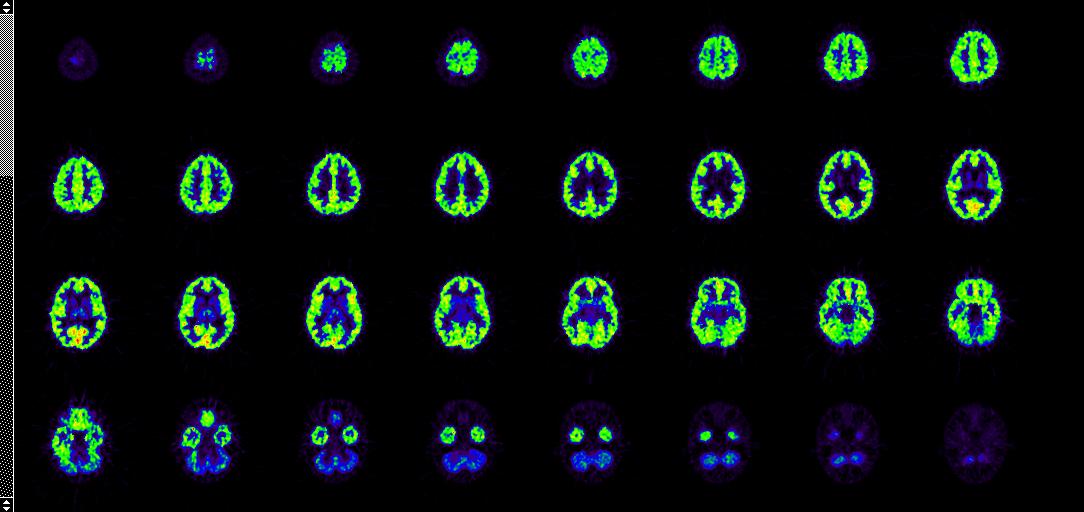

ECAT 6.3 format, unit depending on the calculation model. Each pixel values (color) corresponds to a certain physiological parameter value.

[11C]flumazenil DV image computed with program imglhdv.

[18F]fluoro-deoxy-glucose (FDG) Ki image computed with program imglhki. Image planes (35 slices, thickness 4.25 mm) are animated in top-to-bottom order.